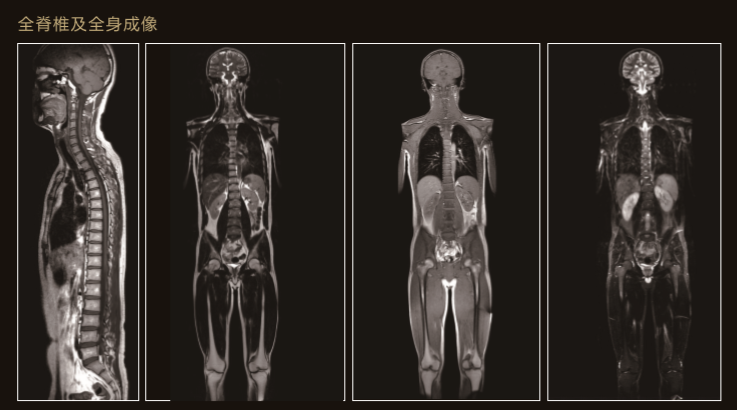

臨 床 圖 集

Apsaras飛天保持高操作性能的同時進一步追求臨床價值

Apsaras飛天不僅采用極高均勻度的磁體系統,還配備了高階勻場系統可大範圍的高階磁場校正,以獲得具有臨床價值的圖像。

Apsaras飛天在保持以往使用便捷的前提下,應用程序支持更全面的臨床應用和發展。